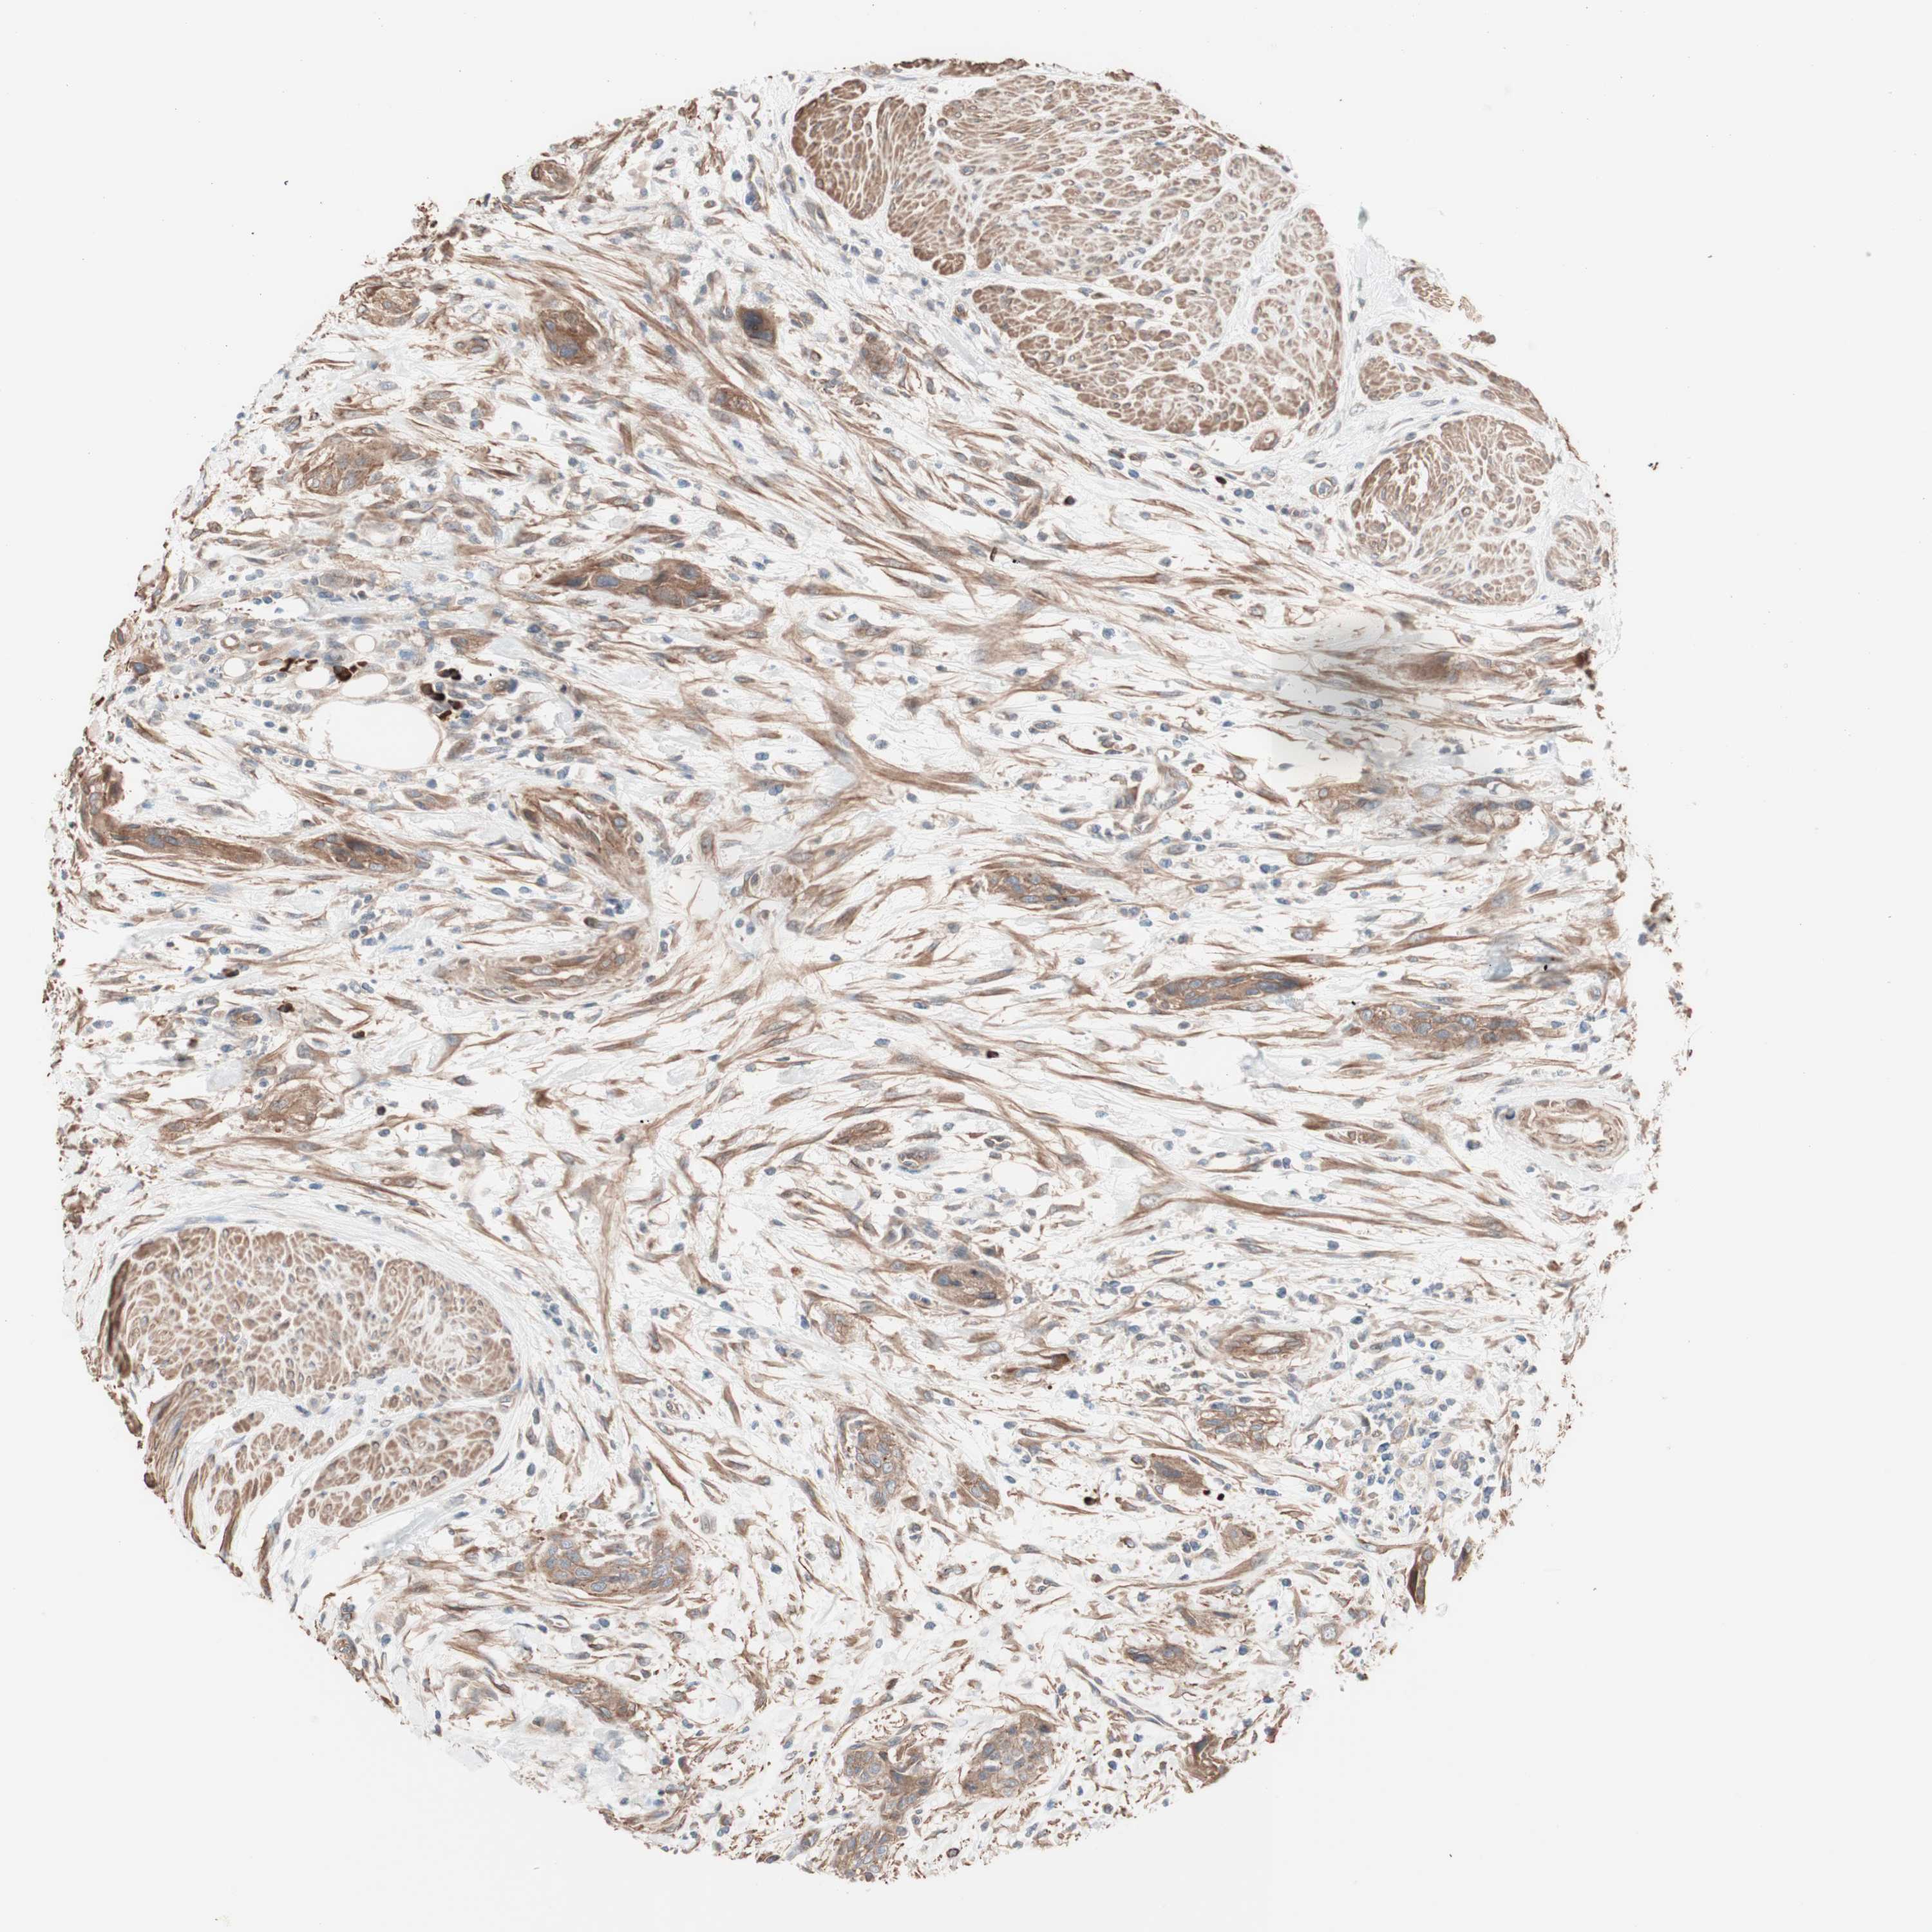

UROTHELIAL CANCER - Protein expressioni

A mouse-over function shows sample information and annotation data. Click on an image to view it in a full screen mode. Samples can be filtered based on level of antibody staining by selecting one or several of the following categories: high, medium, low and not detected. The assay and annotation is described here.

Note that samples used for immunohistochemistry by the Human Protein Atlas do not correspond to samples in the TCGA dataset.

Antibody stainingi

Antibody staining in the annotated cell types in the current human tissue is reported as not detected, low, medium, or high, based on conventional immunohistochemistry profiling in selected tissues. This score is based on the combination of the staining intensity and fraction of stained cells.

Each image is clickable and will lead to virtual microscopy that enables deeper exploration of all samples and also displays staining intensity scores, fraction scores and subcellular localization as well as patient and tissue information for each sample.

Antibody HPA007989

Staining

High

Medium

Low

Not detected

Intensity

Strong

Moderate

Weak

Negative

Quantity

>75%

75%-25%

<25%

None

Location

Nuclear

Cytoplasmic/membranous

Cytoplasmic/membranous,nuclear

Urothelial carcinoma, Low grade

Urothelial carcinoma, High grade